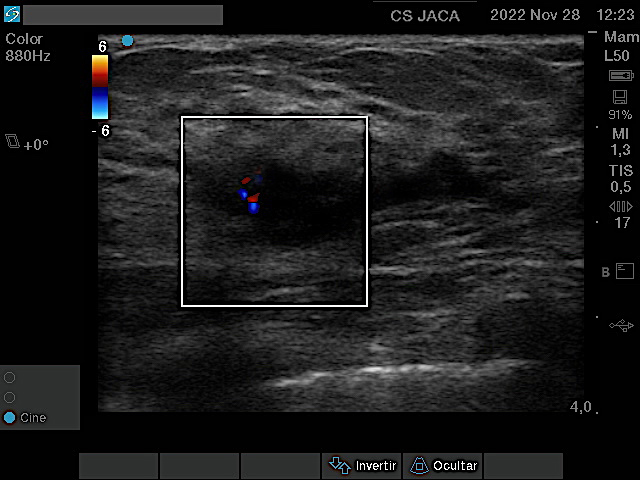

Mostramos las imágenes ecográficas de cada una de esas 5 neoplasias obtenidas desde la Atención Primaria, en modo 2D y tras estudio Doppler. Los tumores variaban de 8 a 30 mm en su eje mas largo. Salvo uno, el resto mostraba características típicas: bordes irregulares, espiculados, estructura hipoecogénica, actividad Doppler interna y ausencia de refuerzo posterior.